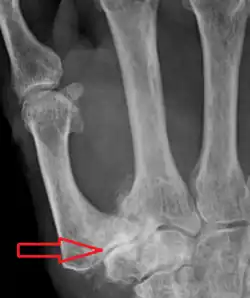

Metacarpal osteotomy

The aim of metacarpal osteotomy is to change the pressure distribution on the TMC joint. The hope is that this will slow the pace of development of osteoarthritis. There is no evidence that this procedure can modify the natural course of TMC OA. Osteotomy may be considered for people with mild arthritis.[24]

During osteotomy, the metacarpal is cut and a wedge shape bone fragment is removed to move the bone away from the hand.[35] Postoperative, the thumb of the patient is immobilized using a thumb-cast.

Possible complications are non-union of the bone, persistent pain related to unrecognized CMC or pantrapezial disease and radial sensory nerve injury.[24]